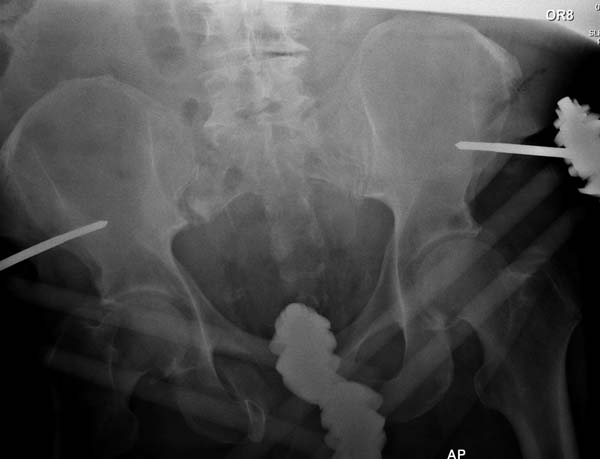

Большое спасибо всем Вам за помощь! Вчера прооперировали пациентку. Выполнили закрытую репозицию левой половины таза на тракционном столе под контролем ЭОП, закрытая фиксация левого КПС двумя каннулированными винтами. Учитывая удовлетворительное стояние отломков лонной и седалищной костей справа, а так же удовлетворительную ширину лона передние отделы стабилизировали системой ЦИТО

Послеоперационные КТ прилагаются

Винты введены в S1

Вроде бы все удалось. хорошо, что фрагмент (как выяснилось из КТ оказался небольшим), но для оценки лучше выкладывать рентген в стандартных проекциях